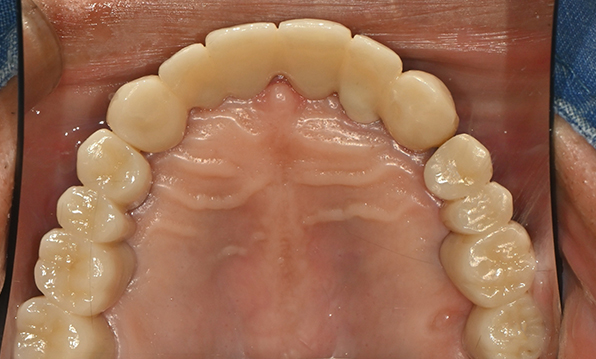

Before & After

Case 01

Before After